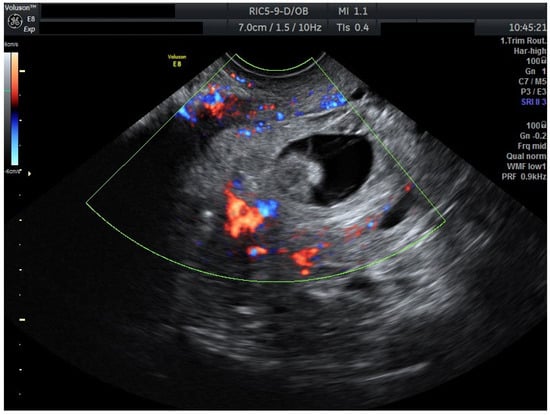

To ensure complete trophoblastic regression in both pregnancies, systemic methotrexate 100 mg was administered intramuscularly at this time (Day 4). A follow-up ultrasound at 48 h (Day 6) confirmed the absence of cardiac activity in both gestations, disorganized gestational sacs, consistent with successful termination. Cervical stromal vascularity identified on color Doppler was suggestive for trophoblastic remnants (Figure 2).

Ultrasound results after methotrexate 100 mg (Day 6). Transvaginal ultrasound evaluation: both sagittal view through the uterus and transverse view through the cervical canal. A total of 48 h after methotrexate 100 mg (Day 6): both embryos without cardiac activity. Cervical stroma with vascularity. Patient information is anonymized.

Serial ultrasound over 72 h documented progressive closure of feeding vessels and reduction in cervical stromal vascularity.

After 72 h, the patient was re-evaluated. Cervical stromal vascularity presented no remaining gross vascularity. Subsequently, starting at the time of this ultrasound evaluation, the patient received misoprostol 0.2 mg intravaginally, every 6 h. This induced partial expulsion of the intrauterine pregnancy into the cervical canal, where it became impacted adjacent to the cervical gestational sac. Despite continued uterotonic administration, the cervical gestation did not expulse. Thus, a suction curettage was performed. The procedure was uneventful, with minimal blood loss, and post-procedure ultrasound confirmed complete evacuation of both gestations and restoration of a normal endometrial cavity and cervical canal (Figure 3).